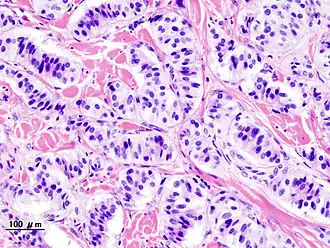

Гистологическая картина

- Патогистология

Панкреатическая инсулинома Окраска инсулиномы Chromogranin A - Histopathology of pancreatic endocrine tumor (insulinoma). Insulin immunostain.